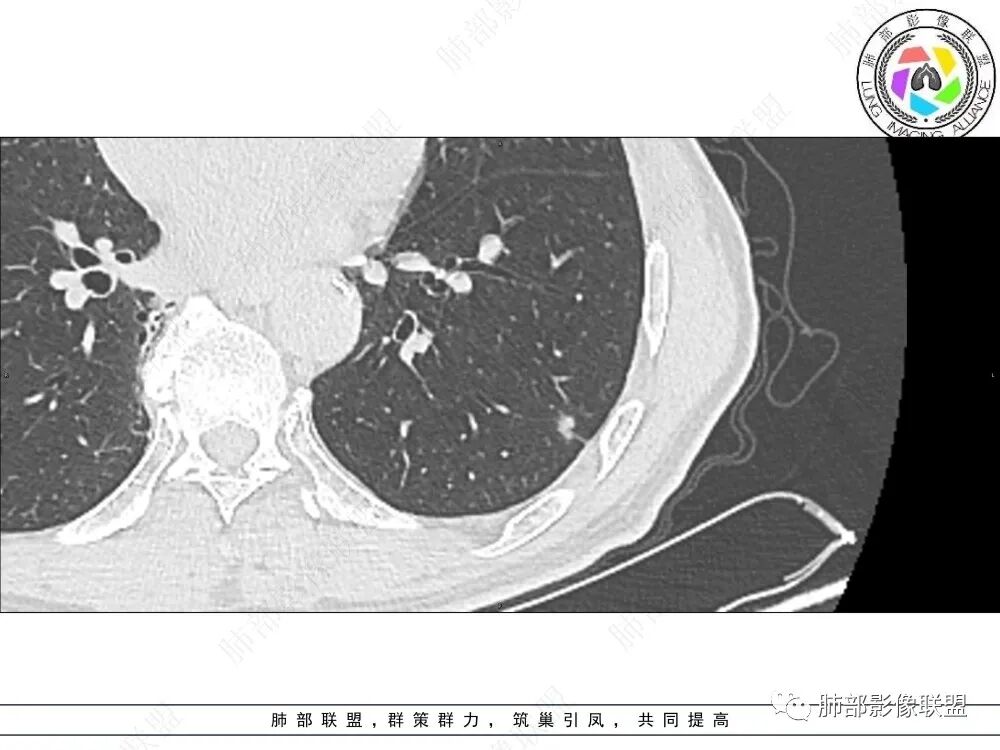

2、影像特点:左肺上叶尖后段病灶结合病史考虑消融术后改变,双肺下叶胸膜下可见多发大小不等的实性结节,周围似乎有晕,边缘平直为主,未见深分叶,部分可见邻近胸膜牵拉,张力不高,增强后呈轻中度强化。

3、总结:中老年男性,间断胸痛就诊,余无明显其他临床体征。既往肺癌病史,定期复查,一年左右双肺新发多发结节,常规需要鉴别炎性肉芽肿和肺癌转移。病灶以胸膜下为主,边界清楚,尽管转移是可以的,但混合磨玻璃时期腺癌相对惰性,短期内难以出现如此转移灶。况邻近胸膜牵拉,这在转移中也相对要少见。病灶多发,但没有新旧不等,没有树芽,病灶及时间线不支持继发性肺结核。病灶散在,胸膜下为主,周围可见少许晕征,部分病灶边缘比较平直,影像上较为符合隐球菌等肉芽肿性炎。

原左肺肺癌消融术后,两下肺新发现数枚实性小结节,胸膜下为主,形态略变扁,病灶周围少许线样牵拉线,增强后环形强化,考虑炎性肉芽肿,淋巴结?结核?隐球菌?鉴别转移。